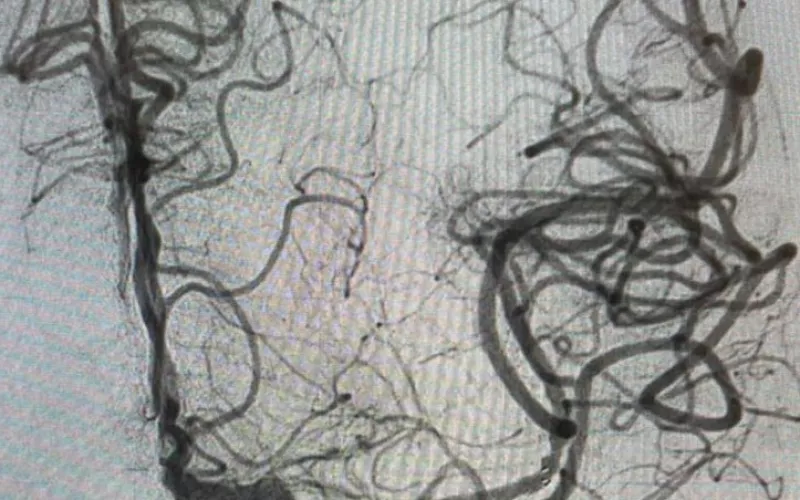

Mediante una resonancia magnética se le detectó la obstrucción de una arteria por un coágulo, fue identificada la zona afectada y se efectuó el rescate que consistió en introducir catéteres desde la ingle hasta el cerebro.

Con este procedimiento se logró que, de nueva cuenta haya circulación sanguínea hacia el cerebro de la derechohabiente; el lenguaje y el movimiento los recuperará paulatinamente conforme progrese con las sesiones de fisiatría, tratamiento farmacológico y cambios en el estilo de vida.